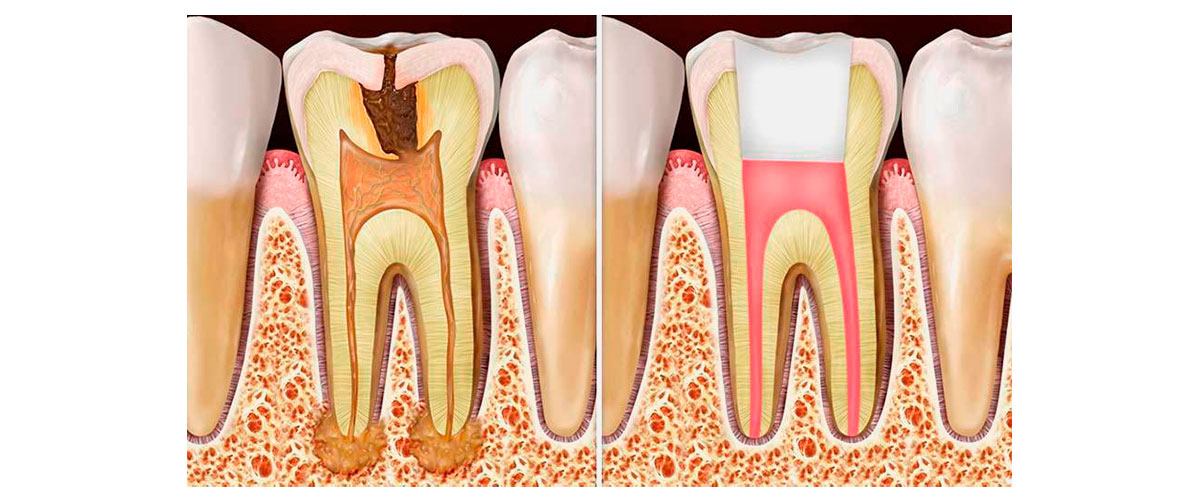

ENDODONCIA MECANIZADA

Los históricos TRATAMIENTOS DE CONDUCTOS afortunadamente ya no son lo que eran. Muchos pacientes han pasado malas experiencias asociándolos con el dolor, sesiones largas, infecciones que no se resolvieron y piezas dentarias que terminaron perdiéndose.

En la actualidad contamos con más y mejores recursos para poder realizar una endodoncia exitosa y de ésta forma salvar una pieza dentaria que sufrió una caries grande o una fractura (que son las causas más comunes por las cuales realizamos este tratamiento).

En OdontoCi contamos con profesionales capacitados y equipamiento acorde para que si necesitas pasar por este tratamiento las cosas salgan como lo esperás. Otro punto importante relacionado a este tema es que, así como cuando se realiza un implante el objetivo final no es el implante en si mismo, si no la resolución protética que será posible instalar en boca por medio de ese implante, cuando realizamos una endodoncia, la hacemos con el objetivo de que esa pieza dentaria o ese resto de pieza dentaria puedan quedar viables para recibir algún tipo de restauración, incrustación o prótesis que permitan devolver la función y estética perdidas. Siguiendo el horizonte de mínima invasión que nos caracteriza, no realizamos pernos metálicos, si no postes de fibra de vidrio e incluso tratamos de evitar colocarlos siempre que se pueda, así como también evitamos realizar coronas siempre y cuando sea posible devolver las estructuras perdidas de una forma más conservadora.

Algunas de las restauraciones que realizamos luego de una endodoncia son:

• ⦿ Restauración con resinas compuestas.

• ⦿ Incrustaciones cerámicas o de resinas con refuerzo cerámico (sector posterior).

• ⦿ Endocrown (coronas sin anclaje intraradicular).

• ⦿ Coronas libres de metal sobre poste de fibra de vidrio.

• ⦿ Carillas cerámicas o de resina (fracturas dentarias en el sector anterior).

OdontoCI es el lugar que estás buscando para resolver tus necesidades odontológicas. Escribinos